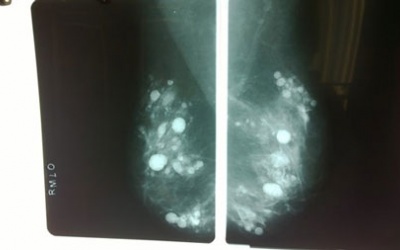

Sau nhiều năm bơm silicon làm đẹp vòng một, người phu nữ ở TP. HCM đã phải gánh chịu hậu quả là sự đau đớn và mất luôn bộ ngực do biến chứng của silicon với hàng trăm khối u lớn...